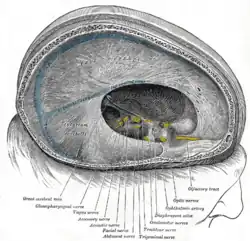

Der Sinus sagittalis superior verläuft in einer gedachten Mittellinie unter dem Schädeldach entlang der sogenannten Hirnsichel (Falx cerebri). Der Sinus sagittalis inferior verläuft im freien Rand der Falx über dem Balken und mündet zusammen mit der Vena cerebri magna in den Sinus rectus. Dieser verläuft gerade nach hinten zum Confluens sinuum, in den auch der von oben kommende Sinus sagittalis superior einmündet. Ebenfalls verbunden ist hier der Sinus occipitalis. Die paarigen Sinus transversi leiten das Blut vom Confluens weiter zur hinteren Schädelbasis, wobei sie sich im Verlauf S-förmig winden und ab dort als Sinus sigmoidei bezeichnet werden. Schließlich münden sie in die tiefen Halsvenen. Der Sinus cavernosus ist ein schwammartiges Netz, das auf dem Keilbein liegt und mit dem übrigen venösen Sinussystem durch jeweils einen Sinus petrosus superior und inferior auf jeder Seite verbunden ist.